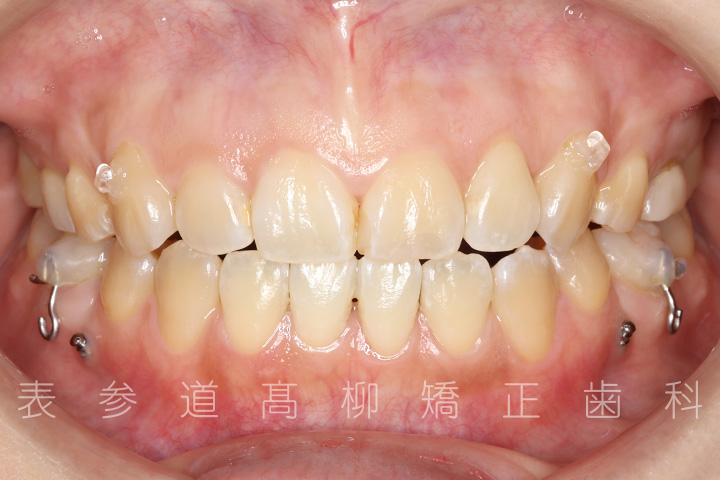

前歯のガタガタ感と開咬でお悩みの患者様の症例をご紹介いたします。

治療前→治療後

術前術後の比較